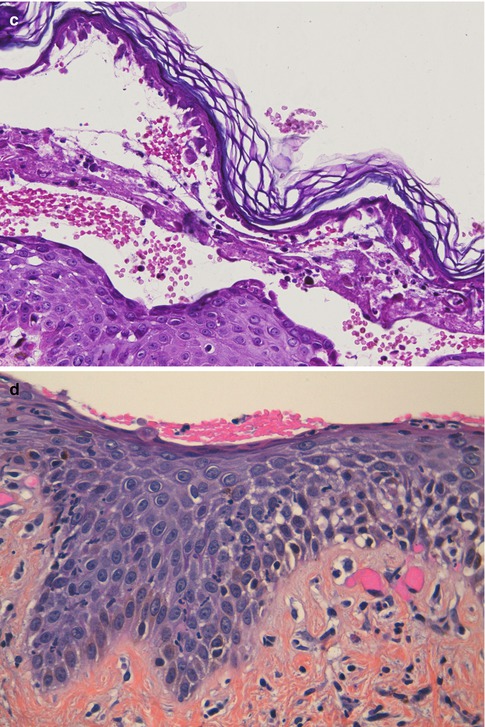

Fig. 16.3

(a) Bullous pemphigoid. Subepidermal blister with abundant eosinophils within the vesicle and in the superficial dermis (hematoxylin-eosin stain; original magnification ×200). (b) Eosinophilic spongiosis. Epidermal spongiosis with the presence of eosinophils. This pattern is not specific for pemphigoid, as it can be observed in other immunobullous disorders, as well as in other inflammatory conditions (hematoxylin-eosin stain; original magnification ×200). (c) Dermatitis herpetiformis. Characteristic microabscesses of neutrophils at the tips of the dermal papillae (hematoxylin-eosin stain; original magnification ×400). (d) Dermatitis herpetiformis. Subepidermal vesicle with superficial inflammatory infiltrates with abundant neutrophils and the presence of scattered eosinophils (hematoxylin-eosin stain; original magnification ×200). (e) Linear IgA bullous dermatosis. Neutrophils aligning along the basement membrane zone at the edges of a subepidermal blister with abundant neutrophils (not shown in the picture). There is also an associated basal vacuolization (hematoxylin-eosin stain; original magnification ×100). (f) Epidermolysis bullosa acquisita, mechanobullous subtype. Subepidermal blister with nearly absent inflammation (there are scant perivascular lymphocytes) (hematoxylin-eosin stain; original magnification ×40). (g) Epidermolysis bullosa acquisita, inflammatory subtype. Subepidermal blister with abundant inflammatory infiltrates in the superficial dermis and within the blister where neutrophils predominate. There is also nuclear dust, abundant eosinophils, and neutrophils aligning along the basement membrane zone of a sebaceous gland in the deepest part of the biopsy (hematoxylin-eosin stain; original magnification ×200)

Histopathological examination of the vesicles and blisters of bullous pemphigoid (BP) demonstrates subepidermal blisters with abundant eosinophils and variable amount of lymphocytes and macrophages in the superficial dermis [14]. The inflammatory cells are distributed within the subepidermal blister and around the vessels of the superficial vessels (Fig. 16.3a). It is unusual to observe the presence of inflammatory cells in the mid- or deeper dermis, and its presence may favor other entities such as arthropod bite reactions, bullous drug reactions, eosinophilic dermatosis associated with hematologic malignancies, or Wells’ syndrome. When the biopsy has been taken from an old lesion, the histological findings may be those of an intraepidermal blister, due to reepithelialization of the blister floor, and this may lead to confusion with pemphigus. Sometimes in evolved lesions instead, there may be necrosis of the epidermal roof of the blister, leading to confusion with other blistering diseases like erythema multiforme or toxic epidermal necrolysis.

When urticarial or eczematous lesions are biopsied, as well as in the prodromal stages of BP (the so-called urticarial stage of BP), histological findings are less specific. The typical findings will be those of superficial perivascular dermatitis with abundant eosinophils and edema of the papillary dermis, and in some cases, in addition, eosinophilic spongiosis can be observed (Fig. 16.3b) [15]. In the author’s personal experience, the observation of eosinophilic spongiosis with eosinophils aligned along the BMZ in an elderly patient (older than 70 years) is highly predictable of BP.

16.1.2.4 Dermatitis Herpetiformis

The classic histopathological findings in dermatitis herpetiformis (DH) are well known, but cannot be considered specific to this entity. In the initial stages, biopsies show the characteristic pattern of microabscesses of neutrophils at the tips of the dermal papillae with fibrin deposits (Fig. 16.3c). As the lesions evolve, subepidermal vesicles with superficial inflammatory infiltrates (both in the dermis and in the blister) composed of lymphocytes, histiocytes, eosinophils, and abundant neutrophils with nuclear dust can be observed. In these lesions we may observe neutrophilic papillary microabscesses at the edges of the blisters (Fig. 16.3d). However, sometimes the pathological findings are not typical. In evolved lesions the inflammatory infiltrates may show the presence of abundant eosinophils, resembling BP. Some authors have even described a pattern similar to arthropod bites with severe edema in the papillary dermis with a mixed infiltrate by multiple eosinophils and “flame figures” in the reticular dermis [20]. However, in the author’s experience, the most important problem in the histological diagnosis of DH is tissue sampling. Most patients present to the clinic with multiple excoriated lesions caused by scratching, but without any visible vesicle or blister. Therefore, in as much as half of the cases, the biopsy will show nonspecific findings such as spongiotic dermatitis, lichen simplex chronicus, changes of excoriation, prurigo nodularis-like lesions, or lymphocytic infiltrate only with fibrosis in the dermal papillae and ectatic capillaries [21].

16.1.2.5 Linear IgA Bullous Dermatosis

Linear IgA bullous dermatosis (LABD) is characterized by the presence of subepidermal vesicles and superficial inflammatory infiltrates containing abundant neutrophils both in the dermis and in the blister accompanied by a variable number of eosinophils and nuclear dust. These vesicles may be totally indistinguishable from the findings detected in DH. However, on the edges of the vesicle, neutrophils tend to be arranged along the BMZ, and this is associated with basal vacuolization (Fig. 16.3e). These findings are also not specific to LABD, as they can be also found in epidermolysis bullosa acquisita (EBA) and bullous systemic lupus erythematosus (BSLE), among others. In some cases neutrophils form microabscesses in the papillae, indistinguishable from those observed in DH. When comparing these two entities, the number of rete tips with neutrophils with basal vacuolization and the length of the BMZ associated with these findings were greater in LABD than DH, while the number of microabscesses of neutrophils in the dermal papillae was greater in DH than in LABD [22]. However, DIF examination must be done to clearly establish each of the above diagnoses with confidence.

16.1.2.6 Epidermolysis Bullosa Acquisita

Histological examination of lesional biopsies in EBA will show subepidermal blisters with variable inflammatory infiltrates depending on the disease phenotype [23]. In the classical mechanobullous phenotype of EBA, the inflammatory reaction is absent, or there are very few superficial perivascular infiltrates of lymphocytes (Fig. 16.3f). These findings may be similar to those observed in the inherited forms of epidermolysis bullosa or certain forms of porphyria. In the inflammatory phenotype of EBA, in contrast, there are abundant inflammatory infiltrates in the superficial dermis where neutrophils predominate [24]. Neutrophils aligned along the BMZ with basal vacuolization can also be seen both in the epidermis and the adnexal structures. Papillary microabscesses of neutrophils, nuclear dust, abundant eosinophils, and even eosinophilic spongiosis can also be seen, although less frequently (Fig. 16.3g). The differential diagnosis in these cases can be broad and has to be done with BP, MMP, DH, LABD, or BSLE. DIF examination will help to differentiate inflammatory EBA from DH or LABD. Recent studies suggest that the inflammatory phenotype of EBA is the most frequent phenotype (up to two thirds of the patients) [25], and therefore, additional studies will be needed to differentiate these patients from other patients with IgG-mediated subepidermal blistering diseases.

16.1.2.7 Bullous Systemic Lupus Erythematosus

In BSLE the histological findings will be identical to the inflammatory phenotype of EBA. Therefore, the biopsies will show the presence of subepidermal blisters with a neutrophilic infiltrate in upper dermis and/or papillary microabscesses of neutrophils [26–28]. In addition some patients may show basement membrane vacuolization and nuclear dust [29].